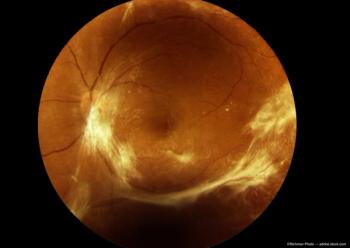

Diabetic Retinopathy

Understanding how the intricate networks of blood vessels in the eye and brain are formed ultimately could inspire new treatments for conditions like diabetic retinopathy and stroke.

While it fell short of the primary endpoint of improvement of non-proliferative diabetic retinopathy (NPDR) of at least 2 Diabetic Retinopathy Severity Scale (DRSS) levels as of week 36, DURAVYU did demonstrate stable or improved disease severity with reduced rates of NPDR in 9 months.

At this year's ARVO meeting, Paolo Silva, MD, presented data on Protocol AA on behalf of the DRCR Retina Network and the effect of diabetic retinopathy lesion location and severity on the risk for progression in the long term.

The DR:EAM trial will evaluate topically delivered OTT166 eye drops in adult patients with moderately severe to severe non-proliferative diabetic retinopathy (NPDR) or mild proliferative diabetic retinopathy (PDR) with minimal vision loss.